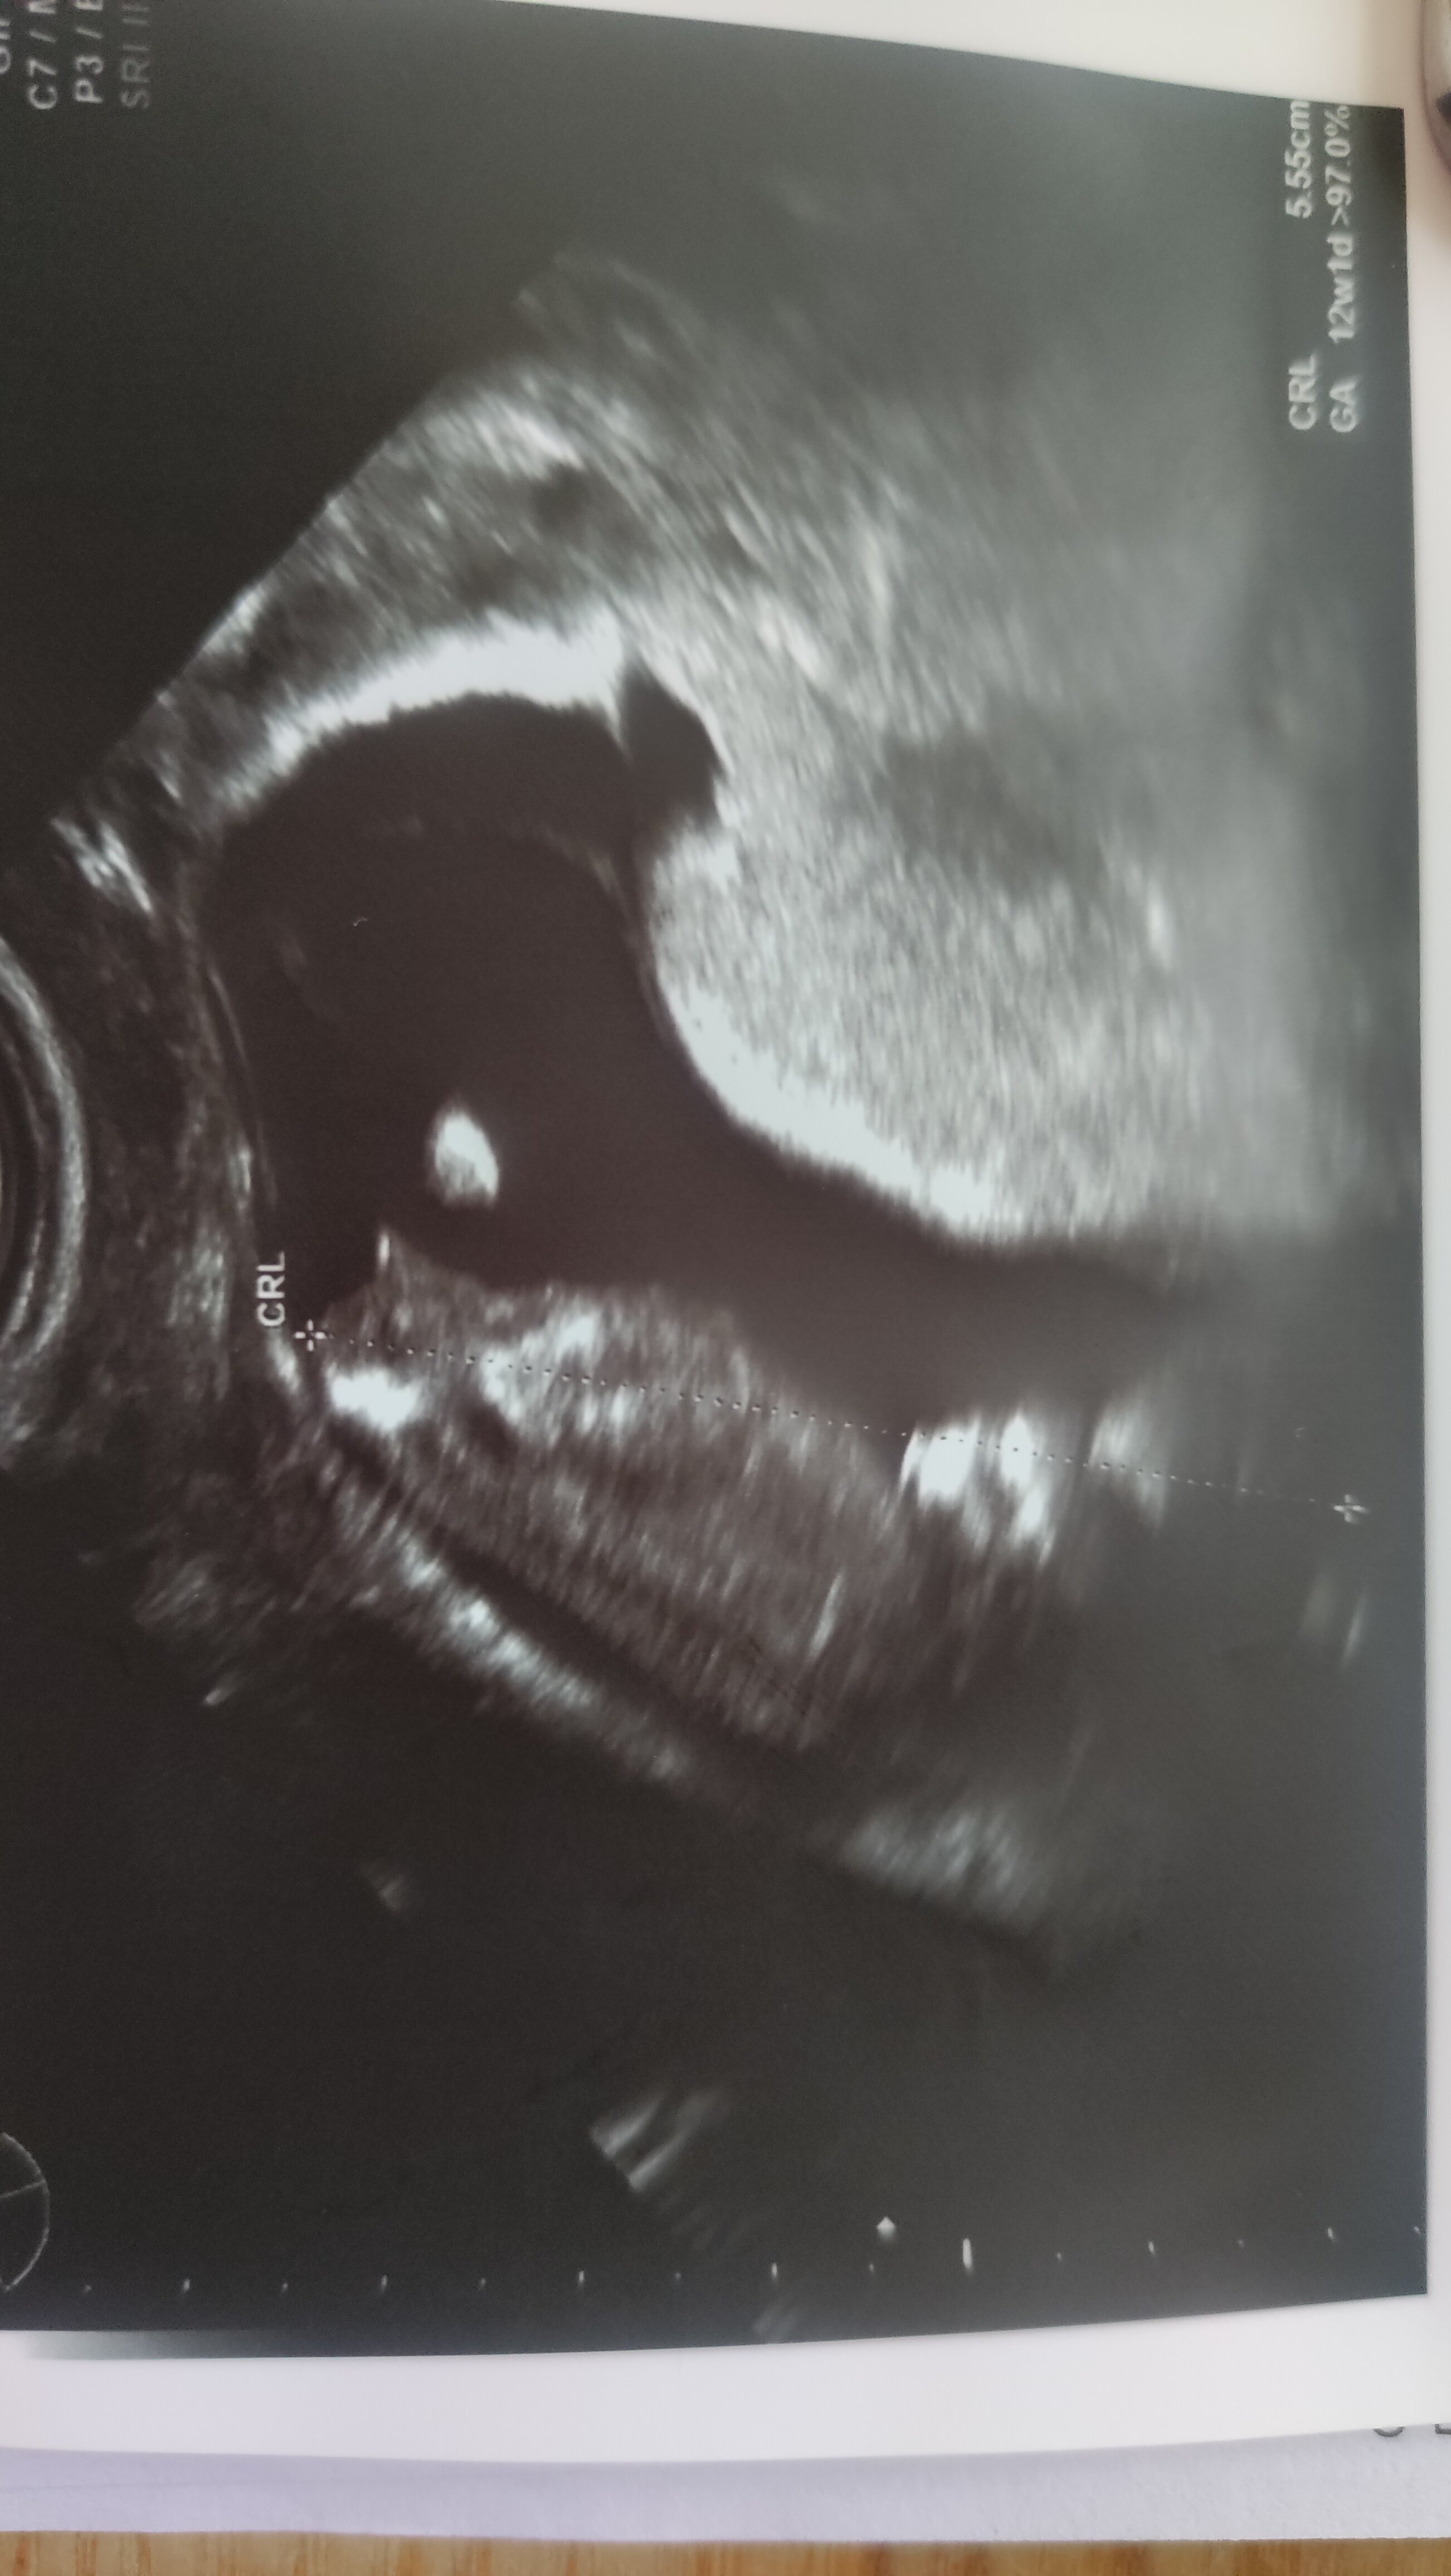

Cieszę się że u was badania prenatalne ok. My też już po. 57mm szczęści. Wiercilo się okropnie. Ale udało się pomierzyć wszystko.

IMG_20210723_172205.jpg

Cieszę się że u was badania prenatalne ok. My też już po. 57mm szczęści. Wiercilo się okropnie. Ale udało się pomierzyć wszystko. Zobacz załącznik 1297549